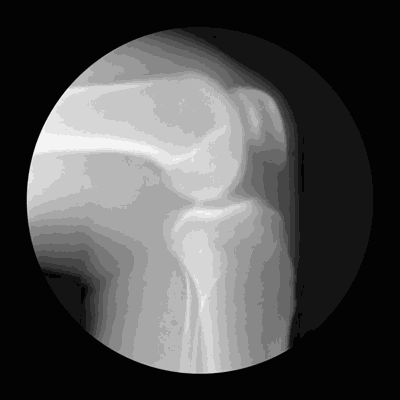

关节病痛,根在软骨,关节软骨由软骨细胞和细胞外基质组成。

骨基质中,胶原蛋白含量非常高,它(胶原蛋白纤维)织成一张网,里面镶嵌着蛋白多糖和水分,还包括少量的矿物质和脂肪,因为有这张网锁住了水分和蛋白多糖,赋予软骨弹性。

胶原纤维开始交联失去弹性,软骨细胞合成蛋白多糖的能力也下降,造成软骨的弹性下降。

关节软骨老化脱落,掉在关节囊里,会刺激关节滑膜上的神经引起疼痛,这些掉在关节里的小块软骨被称为“关节鼠”,就像鞋里进了砂子一样,会硌得疼。

软骨脱落后,软骨下面包着的成骨暴露(骨头和软骨不同,它是有神经和血管的),当它失去软骨这件“外衣”时,神经受到刺激也会疼。